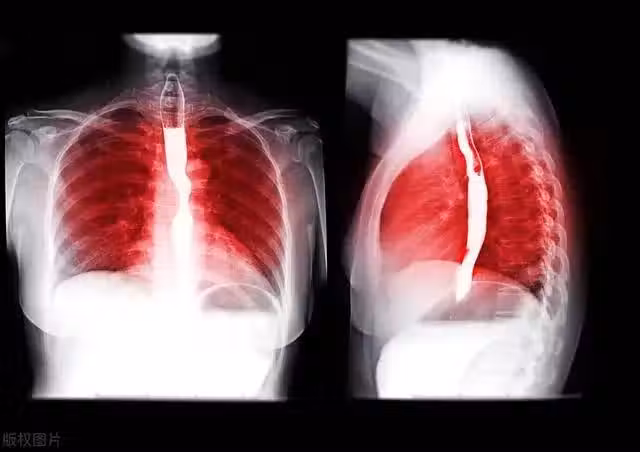

食道癌:很多人誤以為是咽炎!這 5 個症狀,提前逐一揭示